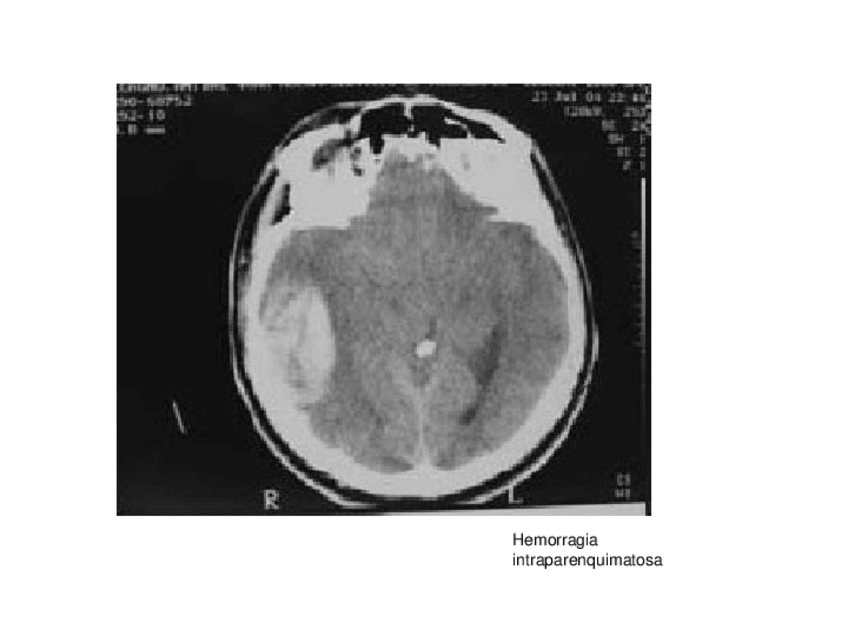

craneo

He publicado nuevos apuntes de Técnicas de Tomografía Computarizada y Ecografía: craneo

CRANI.ppt

tcrani-2011.ppt

craneo-con-anotaciones.pdf

patologia.ppt